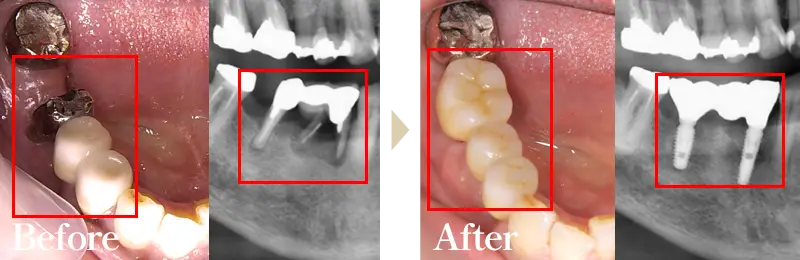

Wデンタルクリニックでは最短2か月で痛みの少ない先進のインプラント治療をご提供することができます。素材は強度にも優れ、身体にも優しい素材になっております。

まるで天然歯のような見た目、噛み応えなどがお勧めポイントです。健康な歯までも削らなくてはいけないブリッジ、違和感が強く噛む力も劣る入れ歯と比べてもメリットが多いのが特徴です。